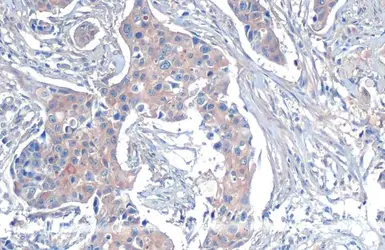

beta Tubulin antibody detects beta Tubulin protein at cytoplasm on human breast cancer by immunohistochemical analysis.

Sample: Paraffin-embedded breast cancer.

beta Tubulin antibody (GTX101279) dilution: 1:500.

Antigen Retrieval: Trilogy™ (EDTA based, pH 8.0) buffer, 15min

The data was published in the journal Cancer Metab in 2014. PMID: 25225614